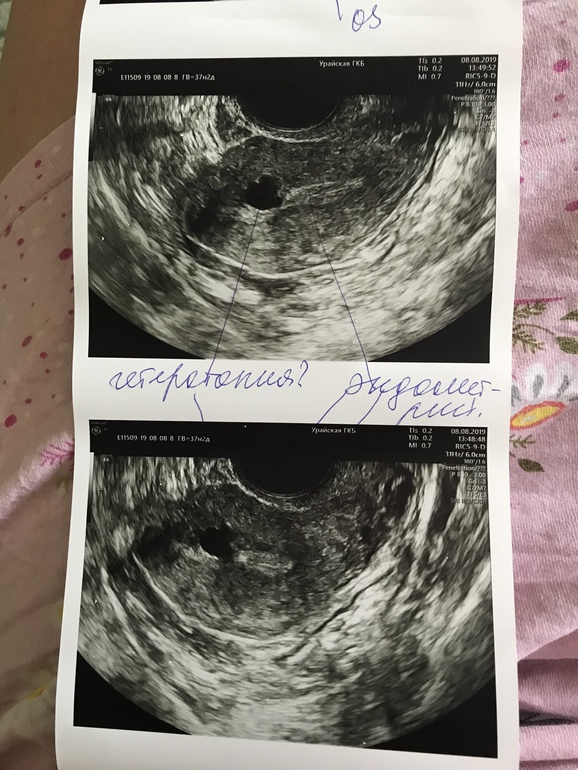

Девочки....помогите разобраться с узи. Цикл 32 дня. В июле была задержка 5 дней, тесты полосатлись, хгч был положительным, на 6 дз (23 июля) пришли скудные мес и шли три дня ( вместо пяти). Потом Тесты отрицательные.

Сходила сегодня 8 августа на узи посмотреть что там

Что это за образование в матке? 😫узист говорит на беременность не похоже...

Узист говорит на беременность не похоже.... вот и незнаю что думать. Но почти см образование...(((( после родов всякие болячки цепляются блин, никогда такого не было.....

Сердце думаю не забьётся. Образование не похоже на яйцо, яйцо ведь кругловатое, а у меня образование какое-то с неровными краями, деформированное...да и в 9мм я думаю там было бы видно уже эмбрион... хотя начитавшись тут, всякое бывает 😄

Думаю может это беременность? 😑 но смущает 9мм образование..... в общем в голове каша малаша